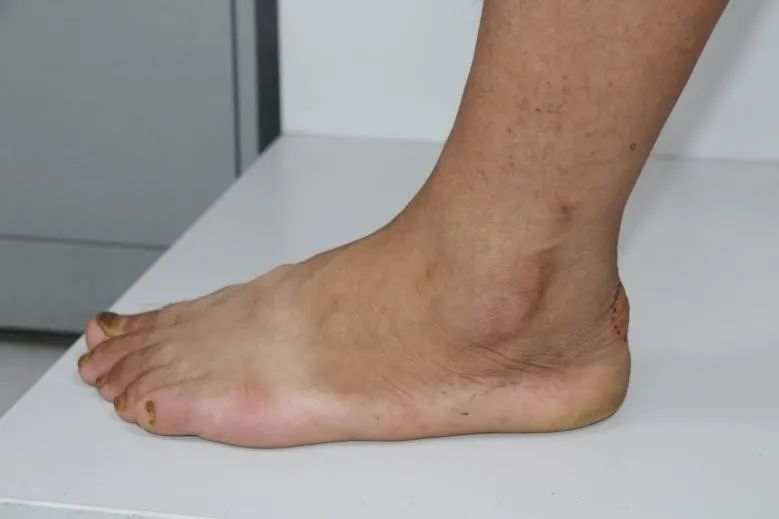

临床表现:跟腱止点部位疼痛不适,运动时疼痛加剧;渐进性病程,后期逐渐表现为任何活动都可引发疼痛。

体检:跟骨结节后方肿胀、压痛;踝关节主动背伸受限和提踵力量减弱;Silverskold试验可为阳性。